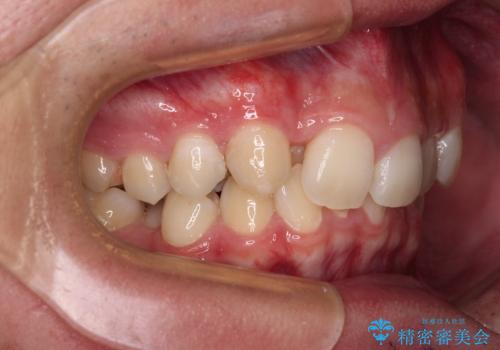

- 今回ご紹介するのは、

「全体的なデコボコ(叢生)」「上下の正中のずれ」 を主訴として来院された20代男性の患者様の症例です。

叢生が強く、歯が並ぶスペースが不足していたため、

上下左右の第一小臼歯を抜歯して、矯正治療のための適切なスペースを確保する計画としました。

叢生によるデコボコがあると、歯ブラシが届かない部分が多くなり、

虫歯リスクの上昇

歯周病の悪化

につながりやすい状態になります。